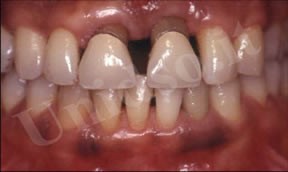

L’ Unità Operativa di Parodontologia e Igiene Orale si compone di 5 sezioni. L’attività’ clinico-assistenziale è svolta da diversi odontoiatri, supportata da igienisti dentali e assistenti alla poltrona, ed è articolata sulla base di appuntamenti programmati. Nell’Unità Operativa di Paradontologia e Igiene Orale del DSMOB si eseguono le seguenti prestazioni odontoiatriche: istruzioni d’igiene orale, ablazione tartaro, full radiografico, terapia dell’alitosi, levigatura radicolare, chirurgia parodontale riparativa, resettiva e rigenerativa e chirurgia plastica dei tessuti molli parodontali.